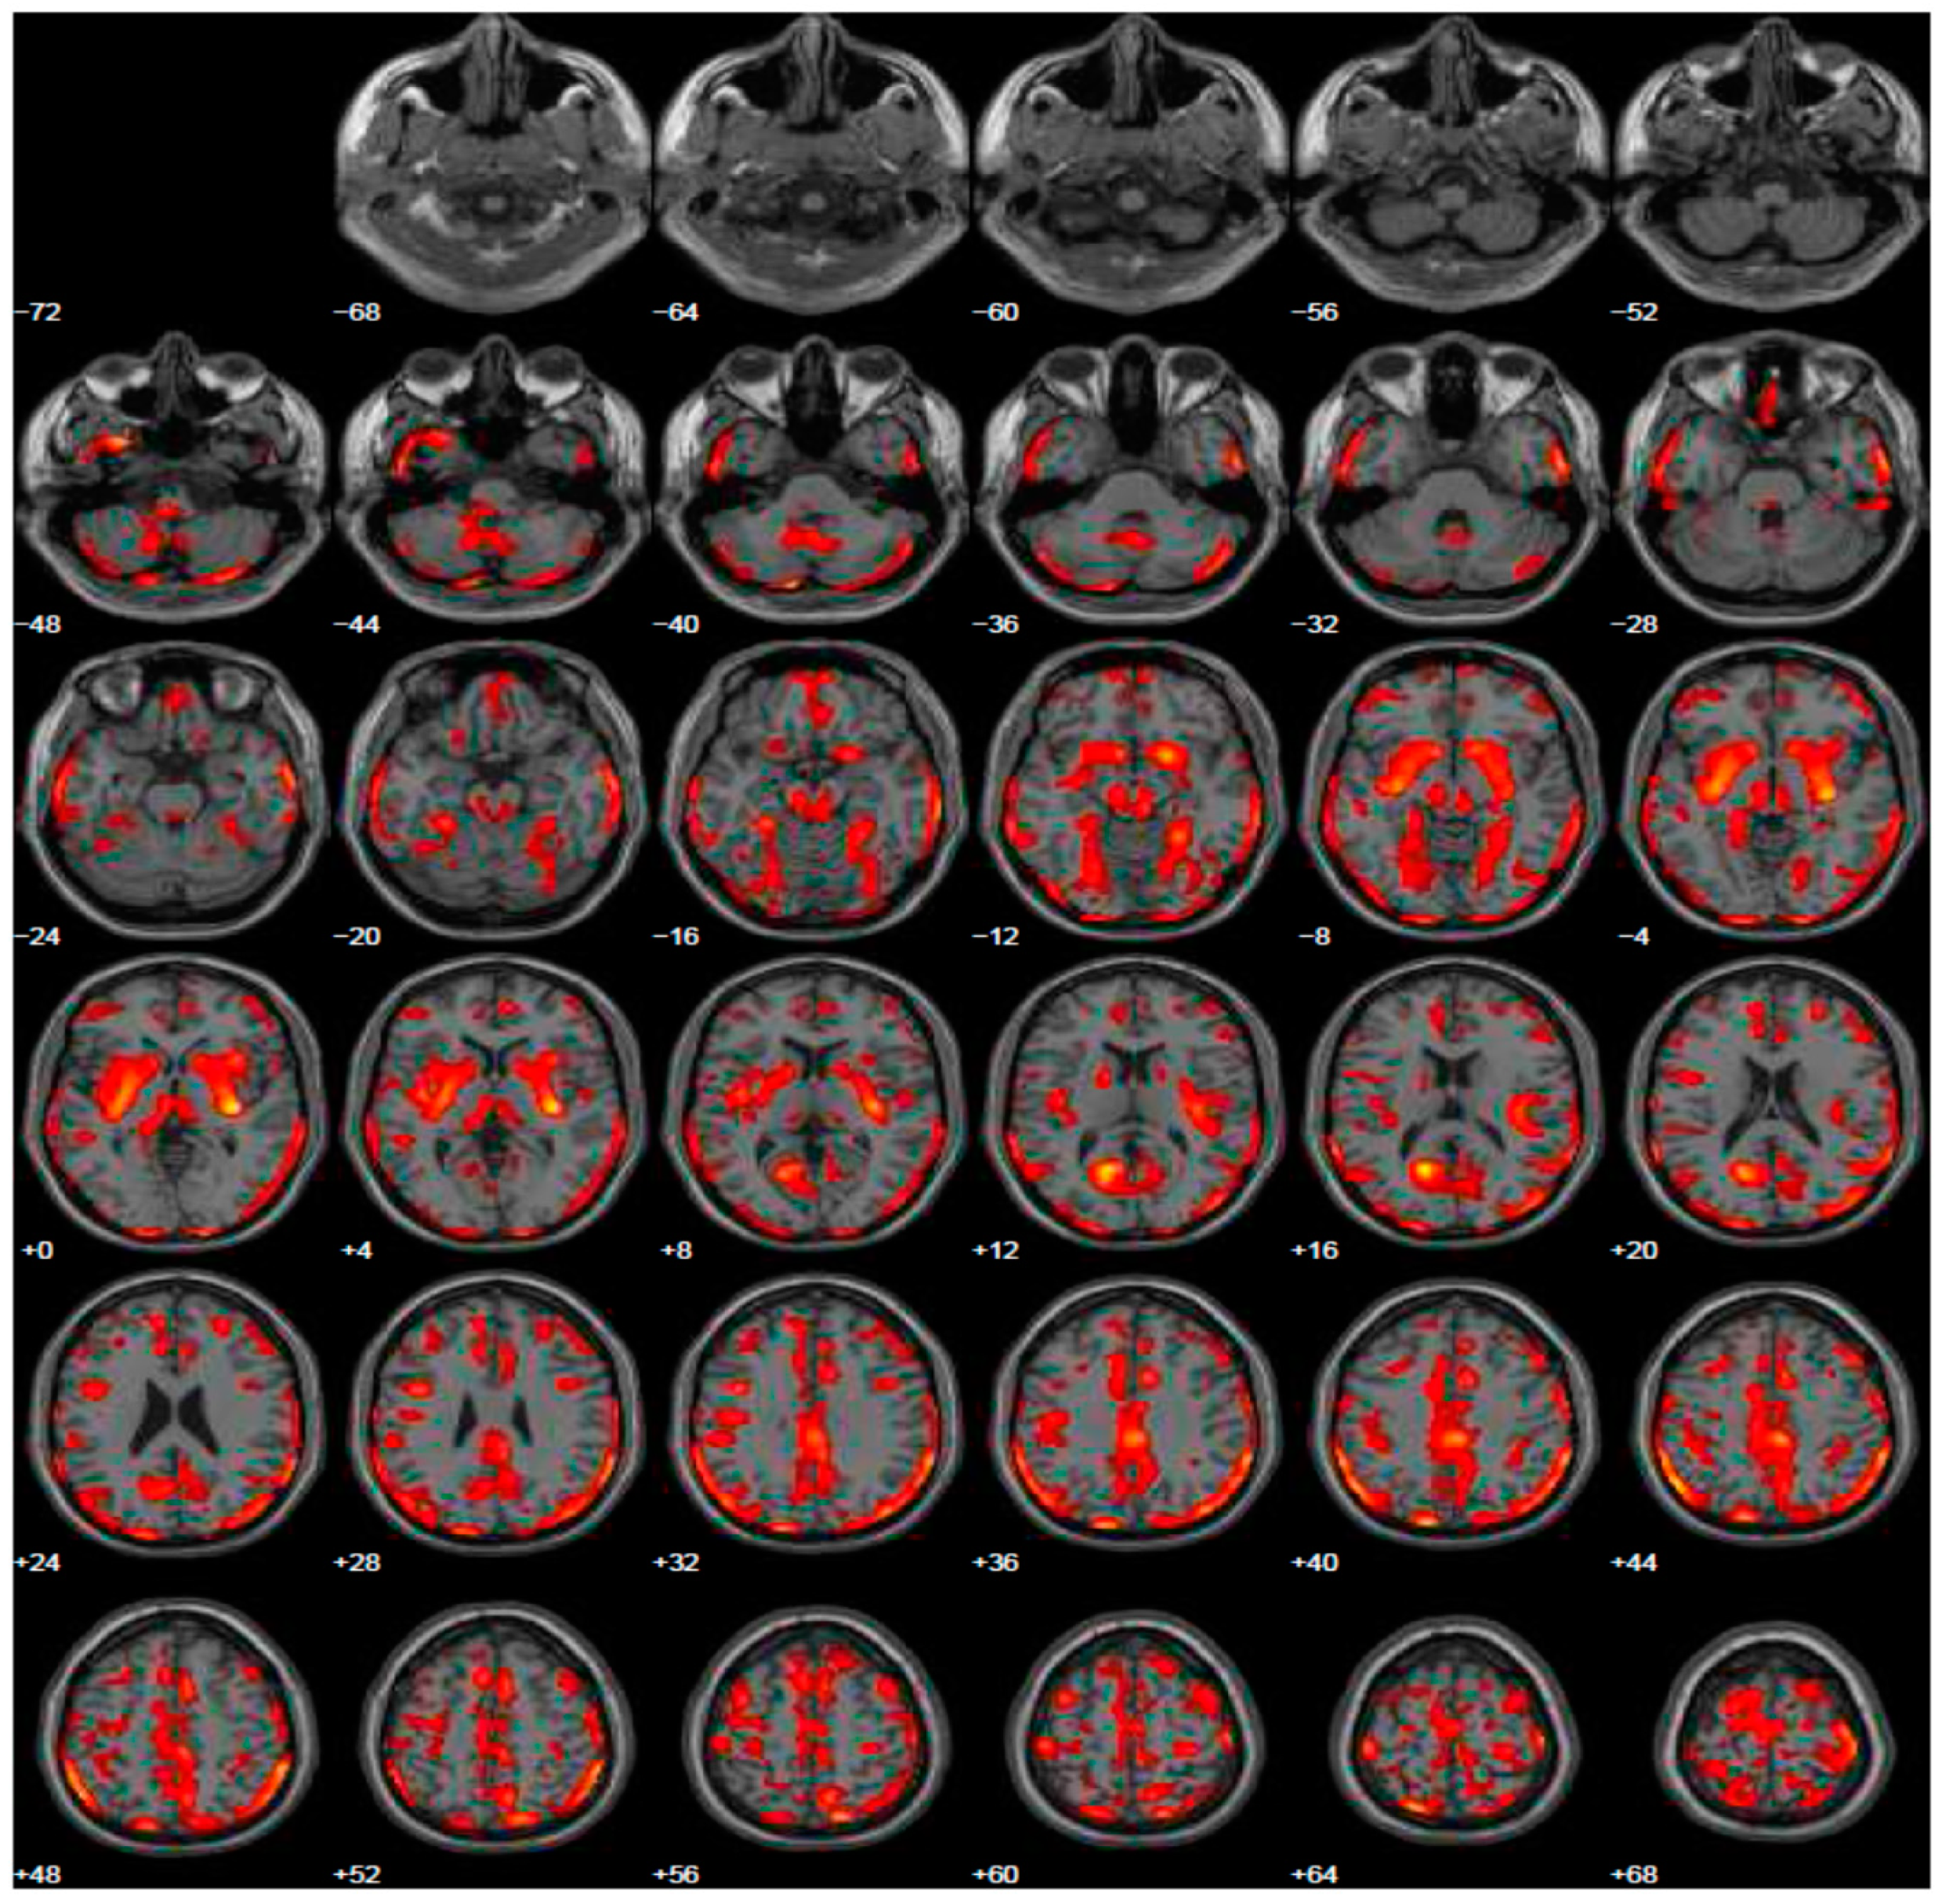

Given the reported ICDs, we changed treatment using L-dopa and prescribed the FDG-PET, to exclude other forms of parkinsonism. The FDG-PET scan showed hypometabolism in many cerebral areas involving, also in this case, the right and left inferior frontal gyrus and part of the prefrontal lateral areas (Figure 3). After the prescription of L-dopa at the dosage of 400 mg daily, we also added venlafaxine for improving depressive symptoms. After a 5-year follow-up period, the patient reported a discrete control of motor symptoms, e.g., he drove his car for more than two hours, and his wife reported a completely disappearance of ICDs, with significant improvement of behavior returning to the same as before starting treatment.

Figure 3.

Brain PET with 18F-FDG. Images highlight brain regions consistently found the analysis (Statistical Parametric Mapping software SPM 5 (p = 0.05). Hypometabolism in the left caudate body and head, left middle temporal gyrus, left superior temporal gyrus, right superior frontal gyrus, left and right inferior parietal lobule, left and right cerebrum sub-lobar insula, left and right superior temporal gyrus, left and right inferior frontal gyrus, right sub-lobar extra-nuclear gray matter, right cerebellar tonsil, right inferior temporal gyrus, left and right middle temporal gyrus, left limbic lobe uncus, left limbic lobe parahippocampal gyrus, right transverse temporal gyrus.